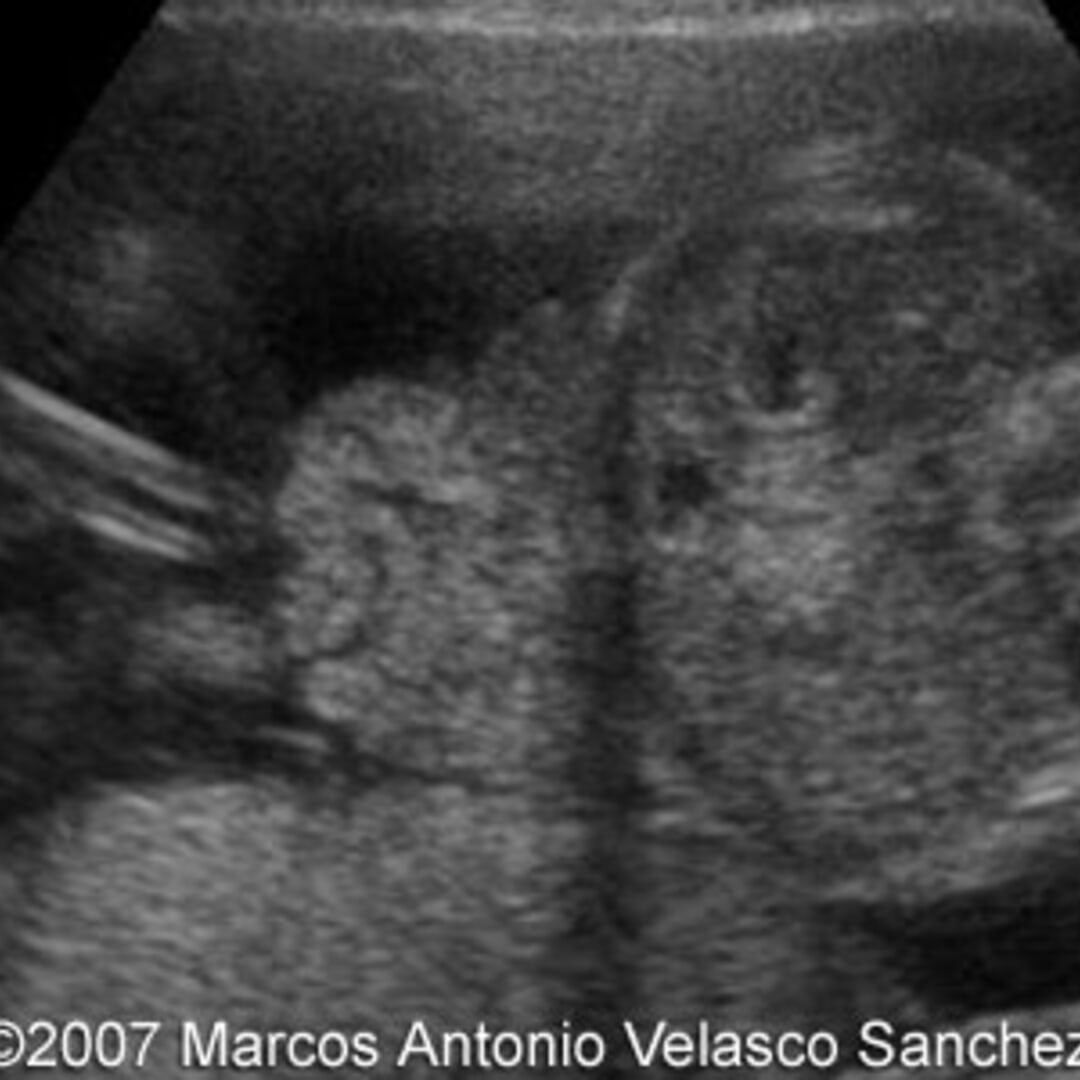

From thefetus.net

📃 Gastroschisis Animal Model Gastroschisis Gastroschisis is characterized by evisceration of abdominal organs through a small defect in the abdominal wall, usually to the right. Large animal experimental models of gastroschisis are inherently limited by expense and length of gestation, making multiple studies and statistical. Recent reports indicate that gastroschisis is increasing in prevalence, whereas omphalocele has remained steady, suggesting that environmental. (a,b) silicone model. Animal Model Gastroschisis.